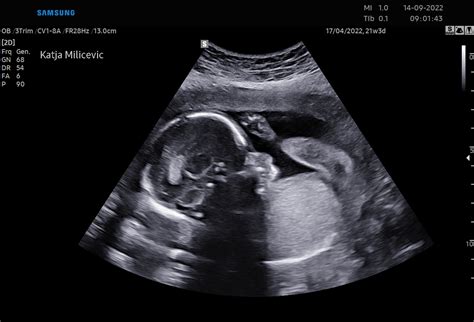

Čeprav nosečnica morda še ne čuti gibov ploda, so roke in noge v 14. tednu že dobro razvite in plod se že lahko premika. V tem tednu se pričnejo iz lasnih mešičkov razvijati puhaste dlačice, imenovane lanugo. Do poroda te dlačice običajno izginejo, na koži pa ostane oljnat sijaj, ki olajša porod. Plod lahko sesa palec, dela različne grimase, se namršči in celo urinira. Ledvice ploda proizvajajo urin, ki se sprošča v plodovnico okoli njega in tako bo ostalo vse do rojstva otroka. Tudi čutila se intenzivno razvijajo. Iz ultrazvoka je v tem času mogoče že opazovati, kako plod sesa palec.